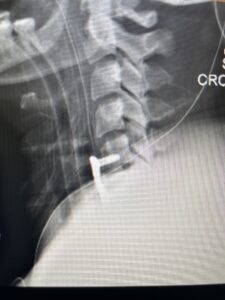

This 36-year-old female who had a long history of neck pain had a history on MRI of a C5-6 bulge. She recently after diving into a pool (not hitting her head on bottom) developed progressive problems with her arms. She had developed spontaneous shocks going down her arms and in the back of her neck. Spontaneous shocks going down the neck and spine is called a Lhermitte’s phenomenon and can occur with spinal cord compression and also with multiple sclerosis. On examination, the patient had long tract weakness of her arms, right greater than left. Her finger extensor weakness was profound on the right. MRI (Fig. 4) of the cervical spine revealed a massive C5-6-disc herniation causing significant cord compression right greater than left with subtle cord signal change. Because of the severe myelopathy, the patient was indicated for surgery. A C5-6 anterior cervical discectomy and fusion was performed (Fig. 5). The patient had a dramatic improvement of her strength in the recovery room.

Fig 5. Intraoperative Lateral Cervical X-Ray demonstrating C5-6 ACDF